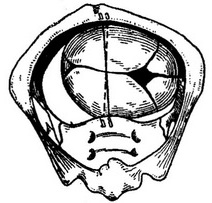

Як тільки передня тім'яна кістка мине лонное зчленування, починає опускатися, зсковзуючи з мису, задня тім'яна кістка, звернена до крижів. Передній асінклітізм, таким чином, вирівнюється - стріловидний шов знову встановлюється близько до середини таза (рис. 54, а, б, в). При цьому вышерасположенная тім'яна кістка (затрималася) завжди заходить під нижчестоящу і передлежачої (рис. 55, а, б).

Рис. 54. Послідовні етапи механізму пологів при плоскому тазі.

а - переднетеменное вставляння; б - просування «задній» половини головки мимо мису; в - потилиця, подолавши вузьке місце, опускаючись, повертається наперед.

Рис. 55.

а - за проходження голівки через вузьке місце потилиця опускається і повертається кпереди; б - заходження кісток черепа при звуженому тазі. Тім'яна кістка, розташована вище, заходить під нижчу тім'яну. Передній асінклітізм.